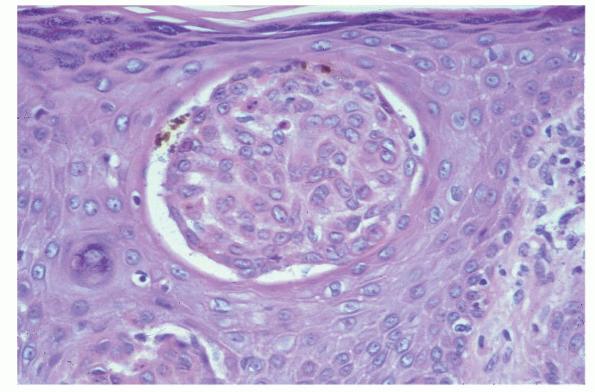

Atlas of skin histopathology

Seborrheic keratoses = التقران الدهني